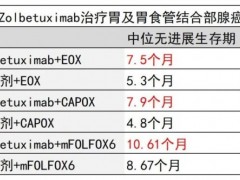

胃癌靶向治疗 2023-09-22

胃癌靶向治疗 2023-09-22

胃癌靶向治疗 2023-08-31

胃癌靶向治疗 2023-08-31